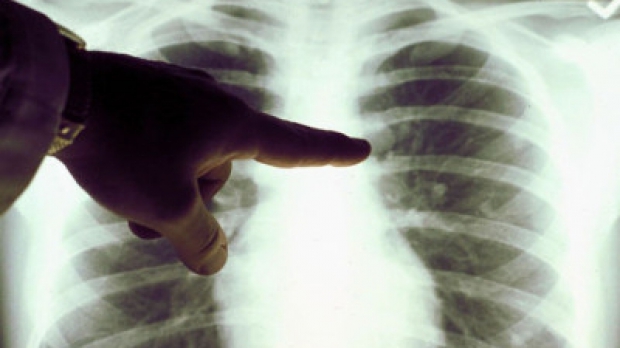

Etichetă: tuberculoză

În doar trei luni, 60 de cazuri noi de tuberculoză, confirmate...

La nivelul județului Gorj, în primul trimestru al acestui an, 60 de persoane au fost diagnosticate cu TBC. La sfârșitul trimestrului au rămas în...

Numărul persoanelor diagnosticate cu TBC, în creştere

Statistic vorbind, la nivelul judeţului nostru există sute de persoane suferinde de tuberculoză. Cifrele înregistrate de Direcția de Sănătate Publică (DSP) Gorj arată o...

De la an la an, numărul persoanelor diagnosticate cu tuberculoză creşte, sute de persoane fiind diagnosticate cu această afecţiune. Unii bolnavi sunt readmişi, afecțiunea...

Peste 70 de cazuri de tuberculoză, confirmate în trei luni

În cadrul Programului de supraveghere și control al tuberculozei, Direcția de Sănătate Publică (DSP) Gorj monitorizează la nivel judeţean derularea activităţilor acestui domeniu, în...

Încă 72 de gorjeni au fost diagnosticați cu TBC

În cadrul Programului de supraveghere și control al tuberculozei, Direcția de Sănătate Publică (DSP) Gorj monitorizează la nivel judeţean derularea activităţilor acestui domeniu, în...

Peste două sute de persoane din județul nostru au fost diagnosticate cu tuberculoză pe parcursul anului trecut. Cu toate acestea, cifrele înregistrate de Direcția...

Statistic vorbind, la nivelul judeţului nostru există sute de persoane suferinde de tuberculoză. Cu toate acestea, cifrele înregistrate de Direcția de Sănătate Publică (DSP)...

În 2013, 336 de gorjeni au fost diagnosticaţi cu tuberculoză

Sute de persoane din judeţul nostru suferă de tuberculoză. Numai anul trecu au fost confirmate 336 cazuri noi. Medicii le recomandă bolnavilor să urmeze...